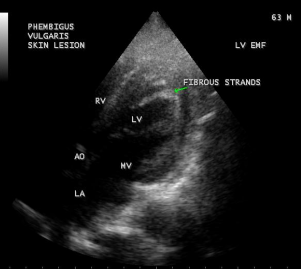

Figure 39: Left ventricular endomyocardial fibrosis in Pemphigus skin lesions in a 63-year old male.

A left ventricular EMF mimicking apical left ventricular hypertrophic cardiomyopathy in a year-old boy as shown in Figures 23, 24 and 25 in a 2-year old male child and an apical right ventricular cardiomyopathy in a year-old female as shown in Figure 26 mimicking as right ventricular EMF have been found by Transthoracic echocardiographic screening. A right ventricular EMF associated with Psoriasis as shown in Figure 3 to7 in a 52- year old male and a left ventricular EMF associated with pemphigus in a 63- year old male as in Figure 39 were detected in this region of Thoothukudi.